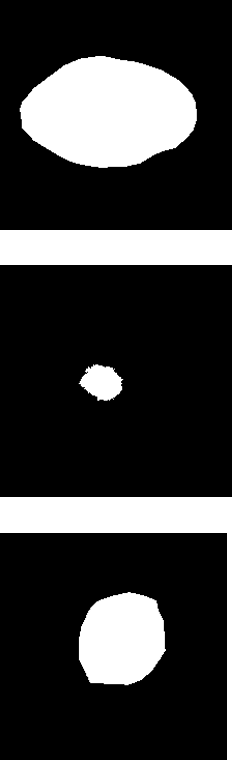

A novel 2D Gaussian Splatting method as shown in Fig. 3 is used to generate segmentation masks, focusing on creating consistent and accurate representations of elliptical lesion boundaries. This method utilizes Gaussian functions to model the shape and scale of lesions, improving the precision of boundary delineation compared to traditional deconvolution techniques. This splatting method is particularly effective in highlighting the asymmetry and irregular borders characteristic of melanoma.

Refer to caption

Figure 3: Illustrative diagram for generating binary masks using 2D Gaussian Splatting. The Gaussian Splats are generated using 66 features: μx,μy,sx,sy,r\mu_{x},\mu_{y},s_{x},s_{y},r

This Gaussian is “splatted” onto the image grid to form the segmentation mask MM. The elements of the covariance matrix are adjusted based on the scale and rotation parameters derived from the network.